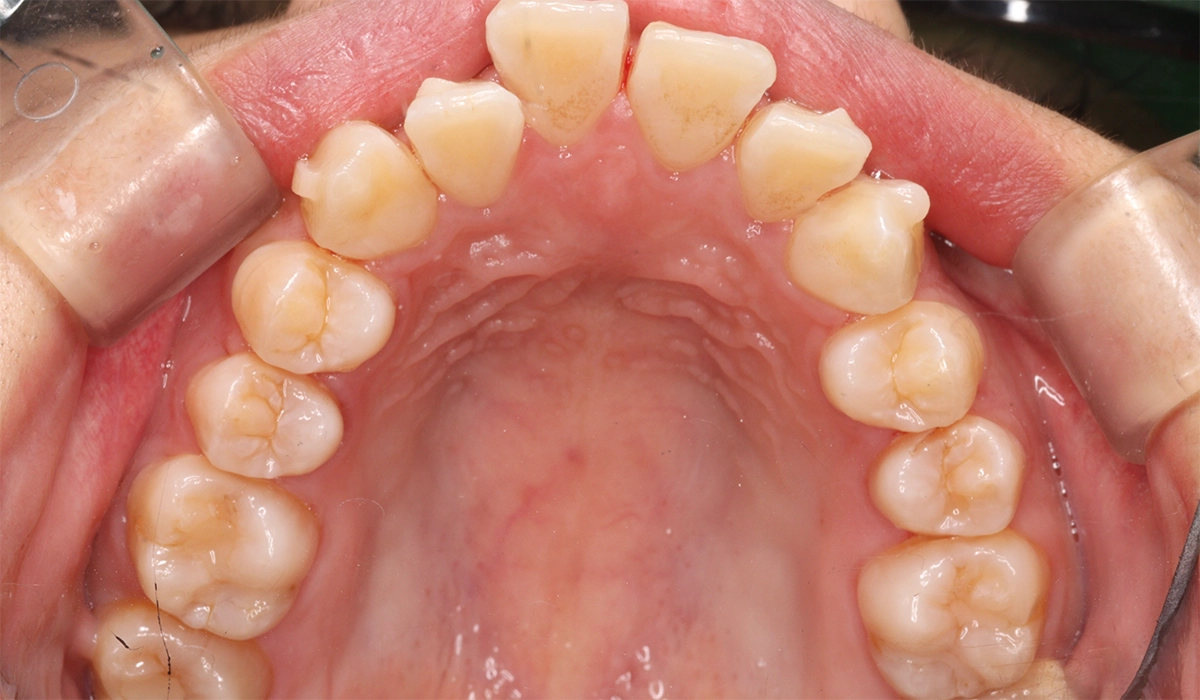

術前:上顎